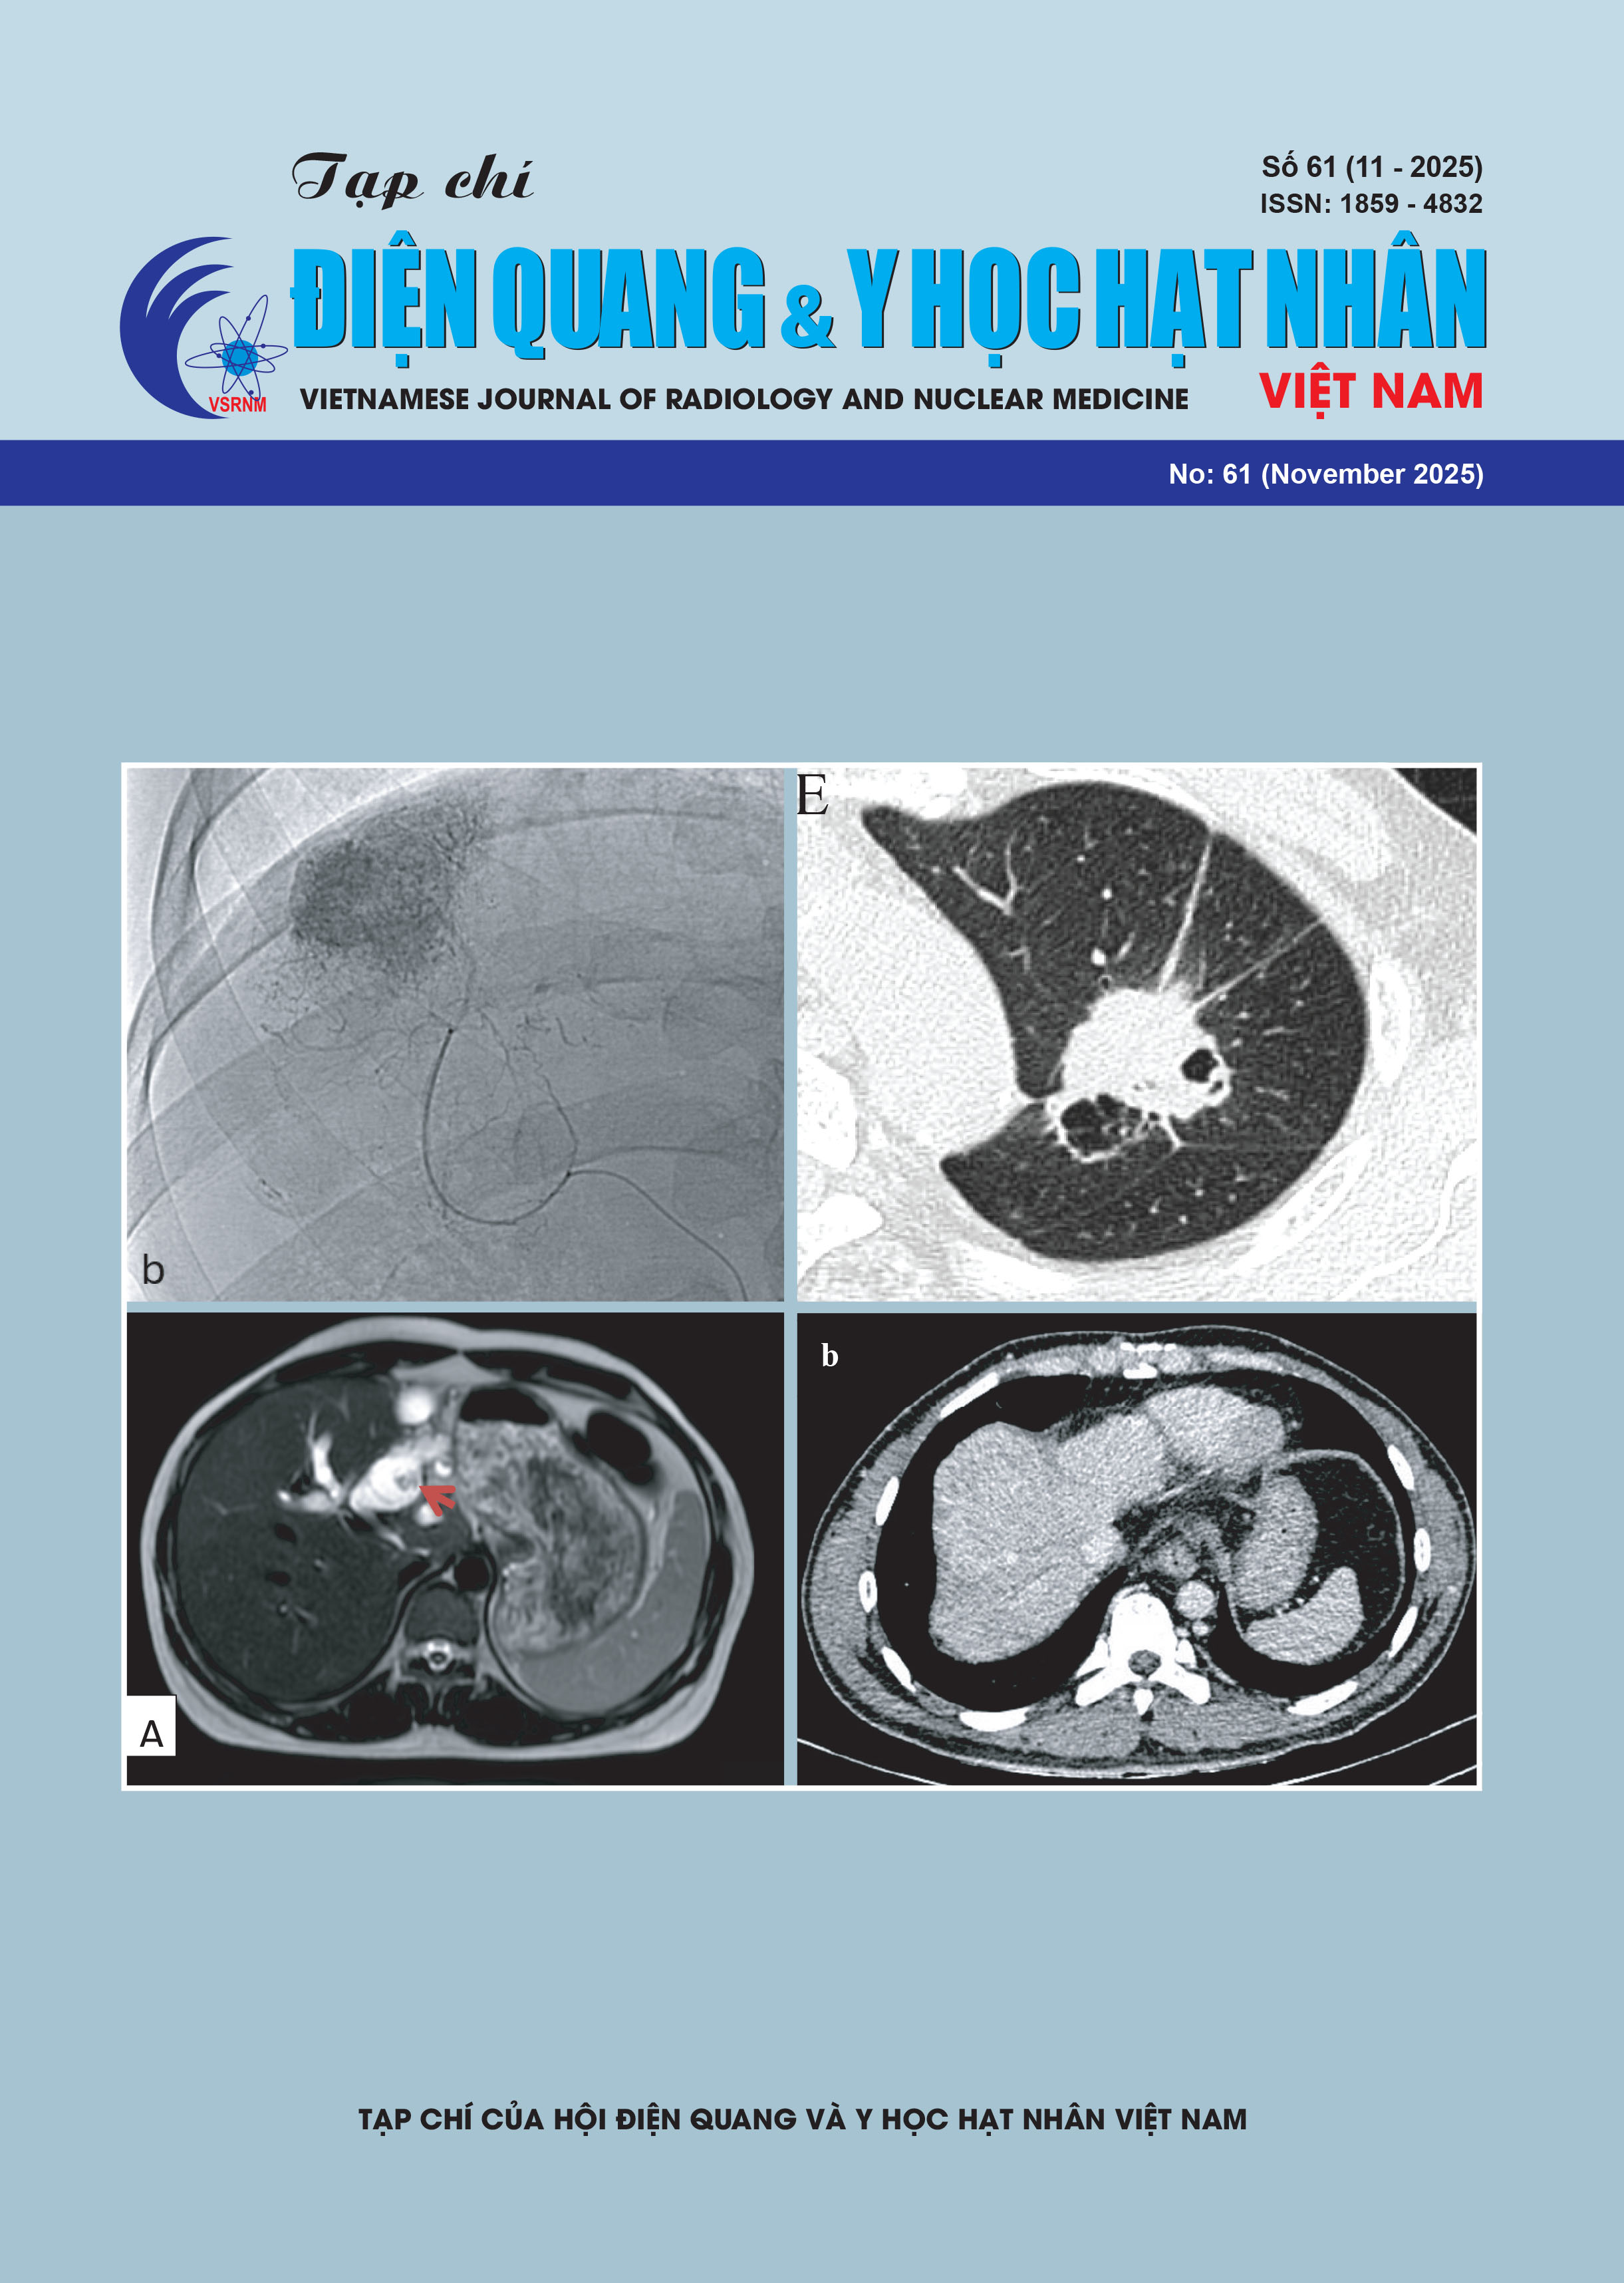

No. 61 (2025)

Treatment Outcomes of Ultraselective Transarterial Chemoembolization for Hepatocellular Carcinoma at Bach Mai Hospital

Comparison of Computed Tomography Characteristics between Pulmonary Adenocarcinoma and Squamous Cell Carcinoma at Bach Mai Hospital

Magnetic Resonance Imaging Features of a Case Series of Intraductal Papillary Neoplasms of the Bile Duct

Primary Klebsiella Pneumoniae Liver Abscess from the Viewpoint of Radiologist: 3 Case Reports and Literature Review

Budd-Chiari Syndrome Role of Imaging Through A Case Serie